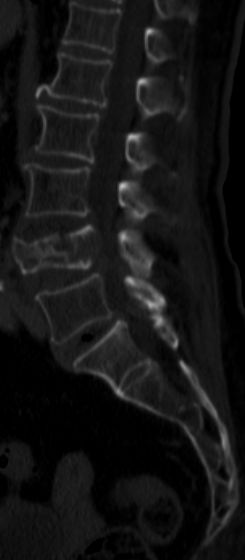

| LWS-Metastase | 86-jährige Frau mit primär ossär metastasiertem Adenokarzinom des linken Oberlappens. CK7 und TTF1 positiv, CDX2,

Vimentin, ZK20, CA125 und P63 negativ.![]() |